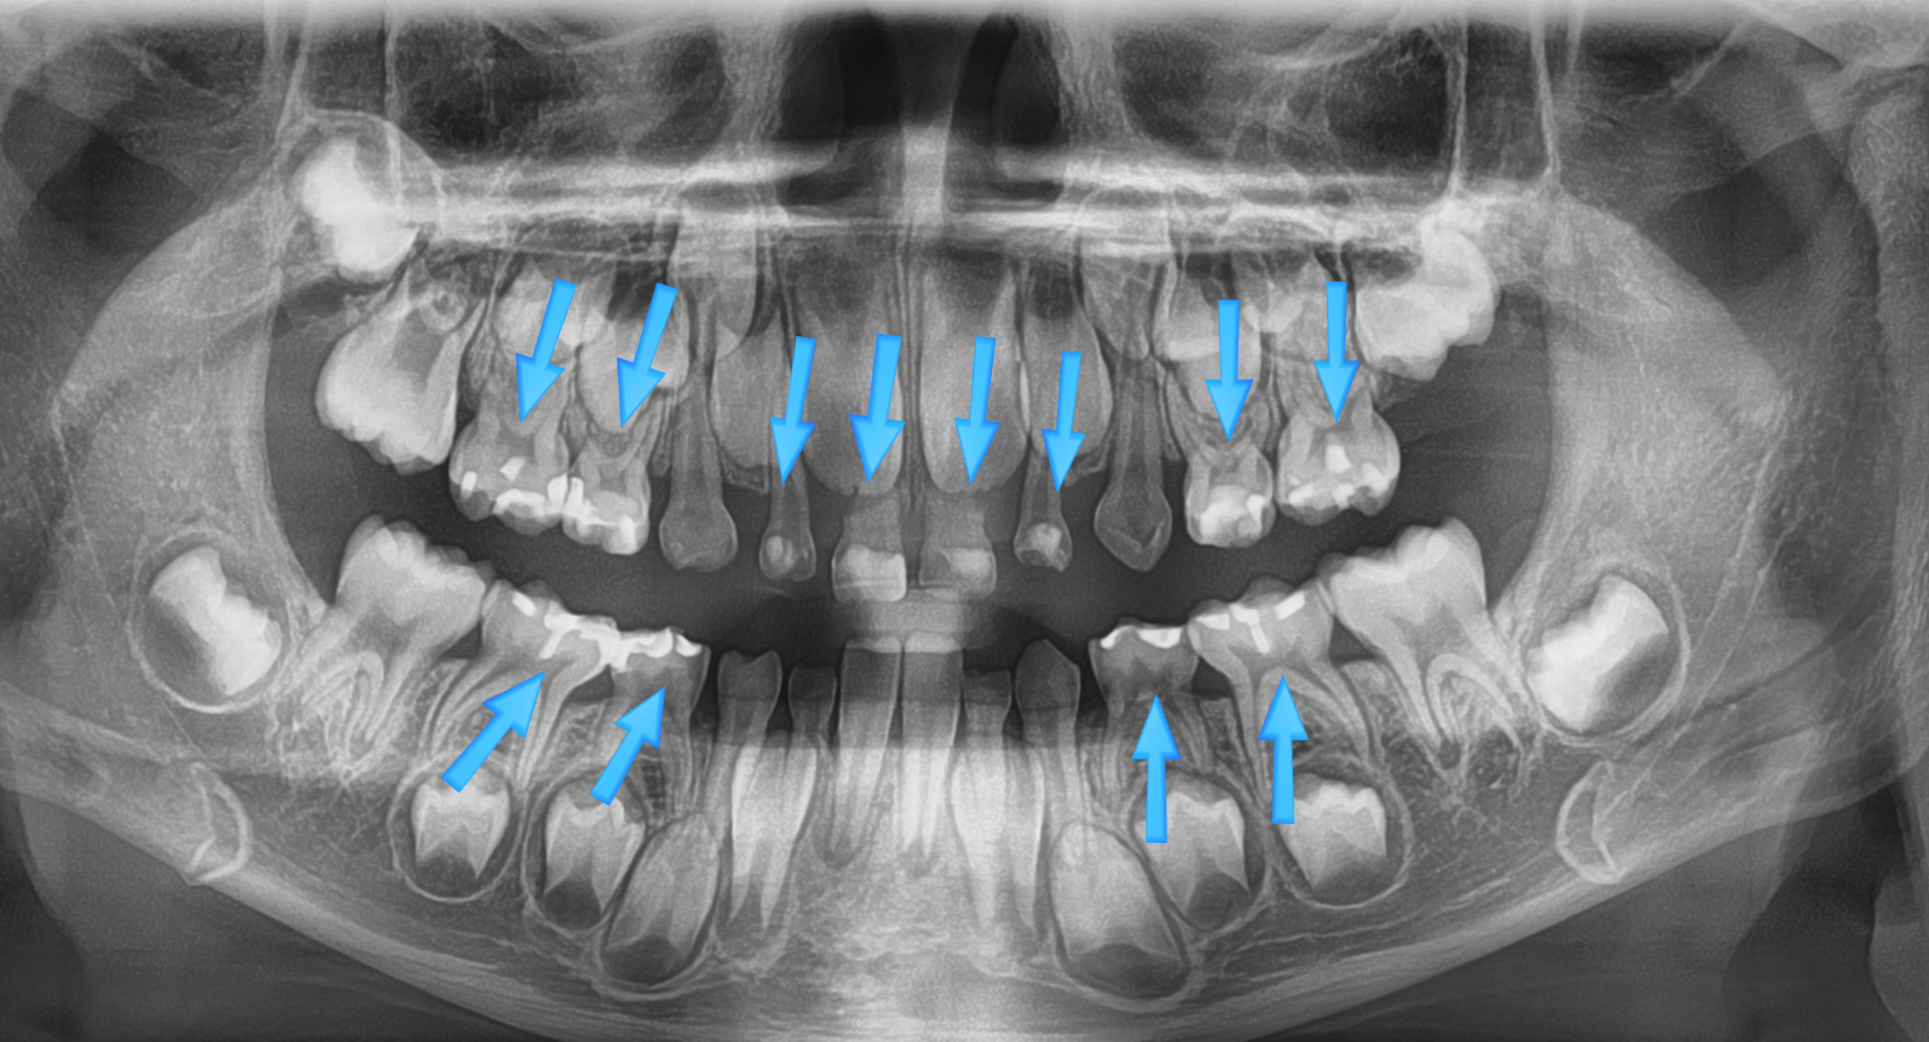

치아 사이충치를 레진으로 8개 치료, 아래 어금니 하나는 지르코니아 크라운으로 치료한 제 큰아이 입니다. (아이에게 동의를 구하고 올립니다.ㅎㅎ)

그런데 치료할 것이 많은데 당시 만 4세 조금 넘은 어린아이였어서.. 겁도 워낙 많은 아이구요, 저는 고민도 하지 않고 수면치료를 택했습니다.